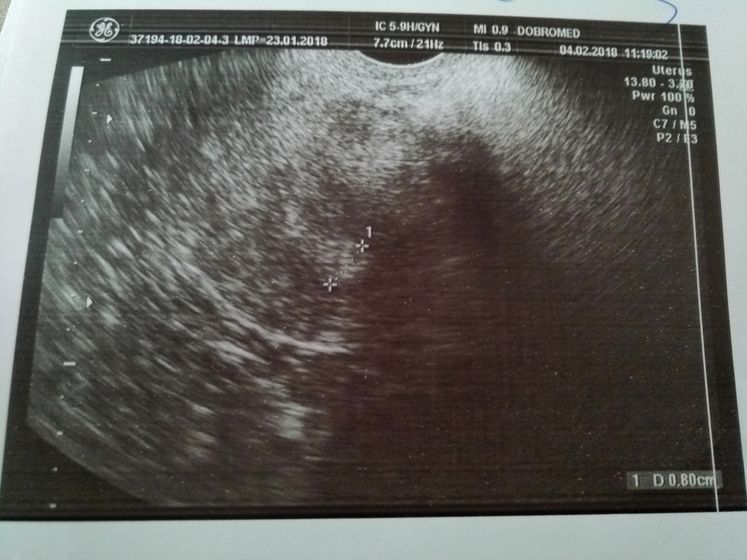

Поехали сегодня в пургу и вьюгу на УЗИ в Добромед(не в восторге) Сделали узи, рассказала что и как врачу, при осмотре было желтое тело, но как я поняла, не совсем то что нужно. В остальном все хорошо, матка, яичники все в норме. Критичного ни чего нет. Послали на ХГЧ завтра за результатом. Если есть, кто разбирается в заключении и в узи, буду рада информации. Тест все еще показывает //

У меня только в 5.5 нед разглялели ПЯ

Ну срок ещё маленький скорее всего, поэтому не увидели